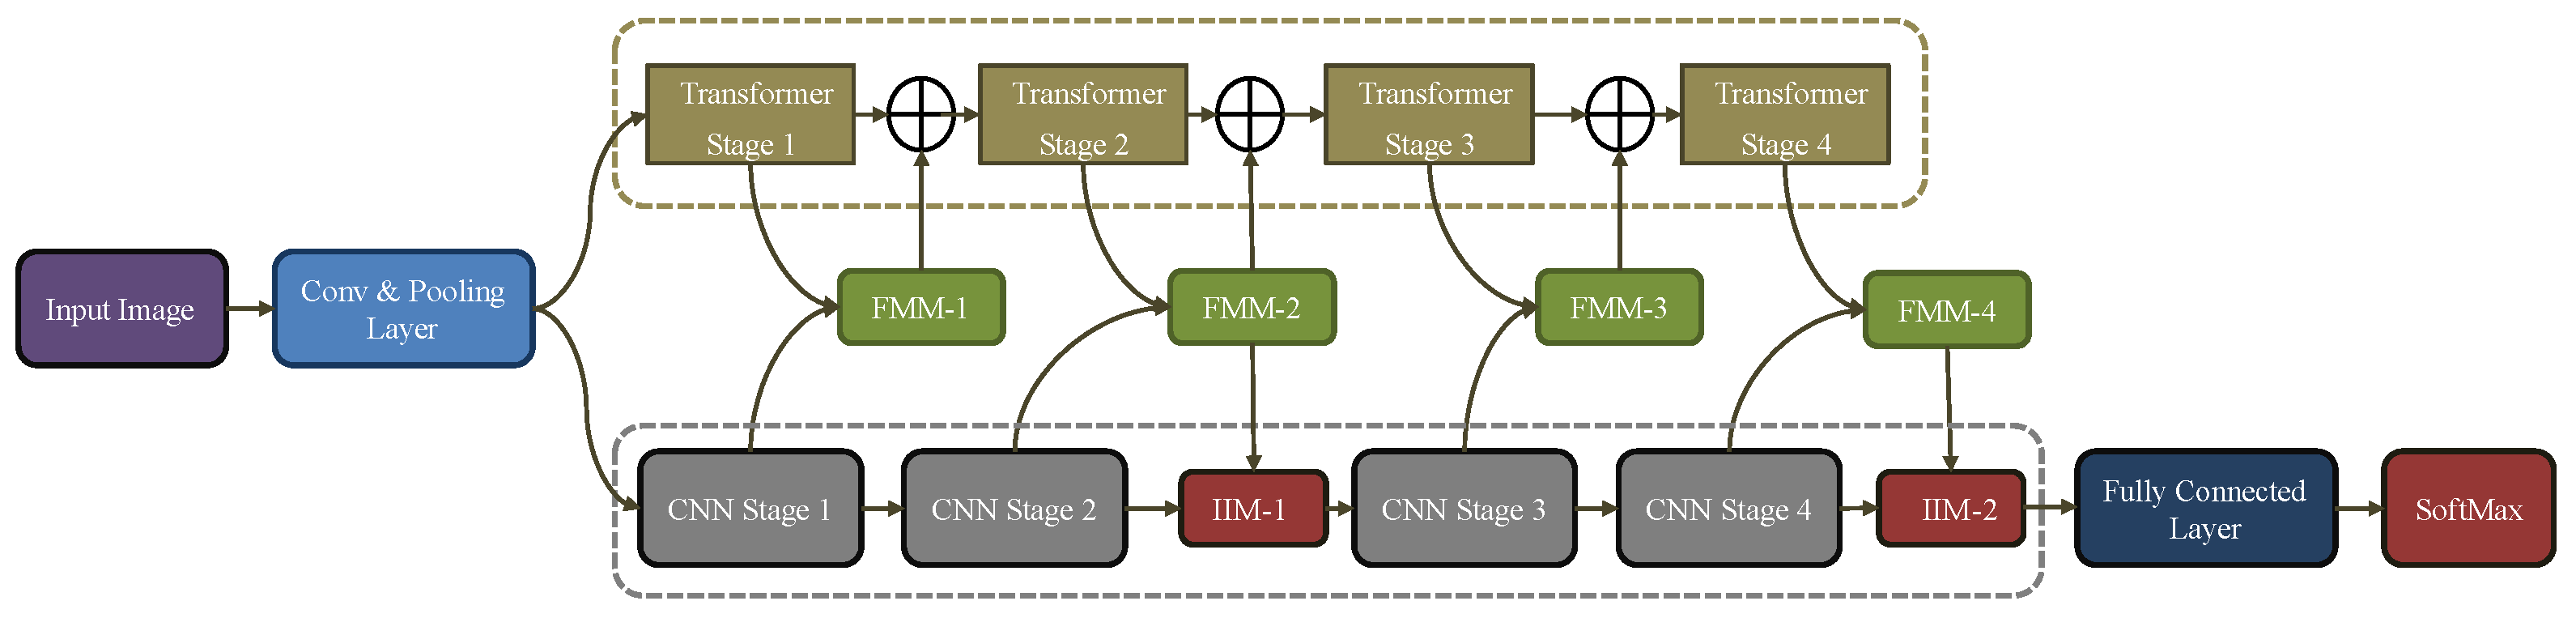

- We propose a hybrid model that extracts local as well as retains global information simultaneously for an effective BT classification.

- In the proposed work the FFM and IMM models are employed, the FFM module is responsible for converting the CNN feature maps to PE, while the IMM is responsible for fusion between the feature maps, PE an adaptive and intelligent process.

3. Research Methodology

3.1. CNN Feature Extractor

3.2. Transformer Pathway

3.3. Feature Merge Module

3.4. Intelligent Merge Module